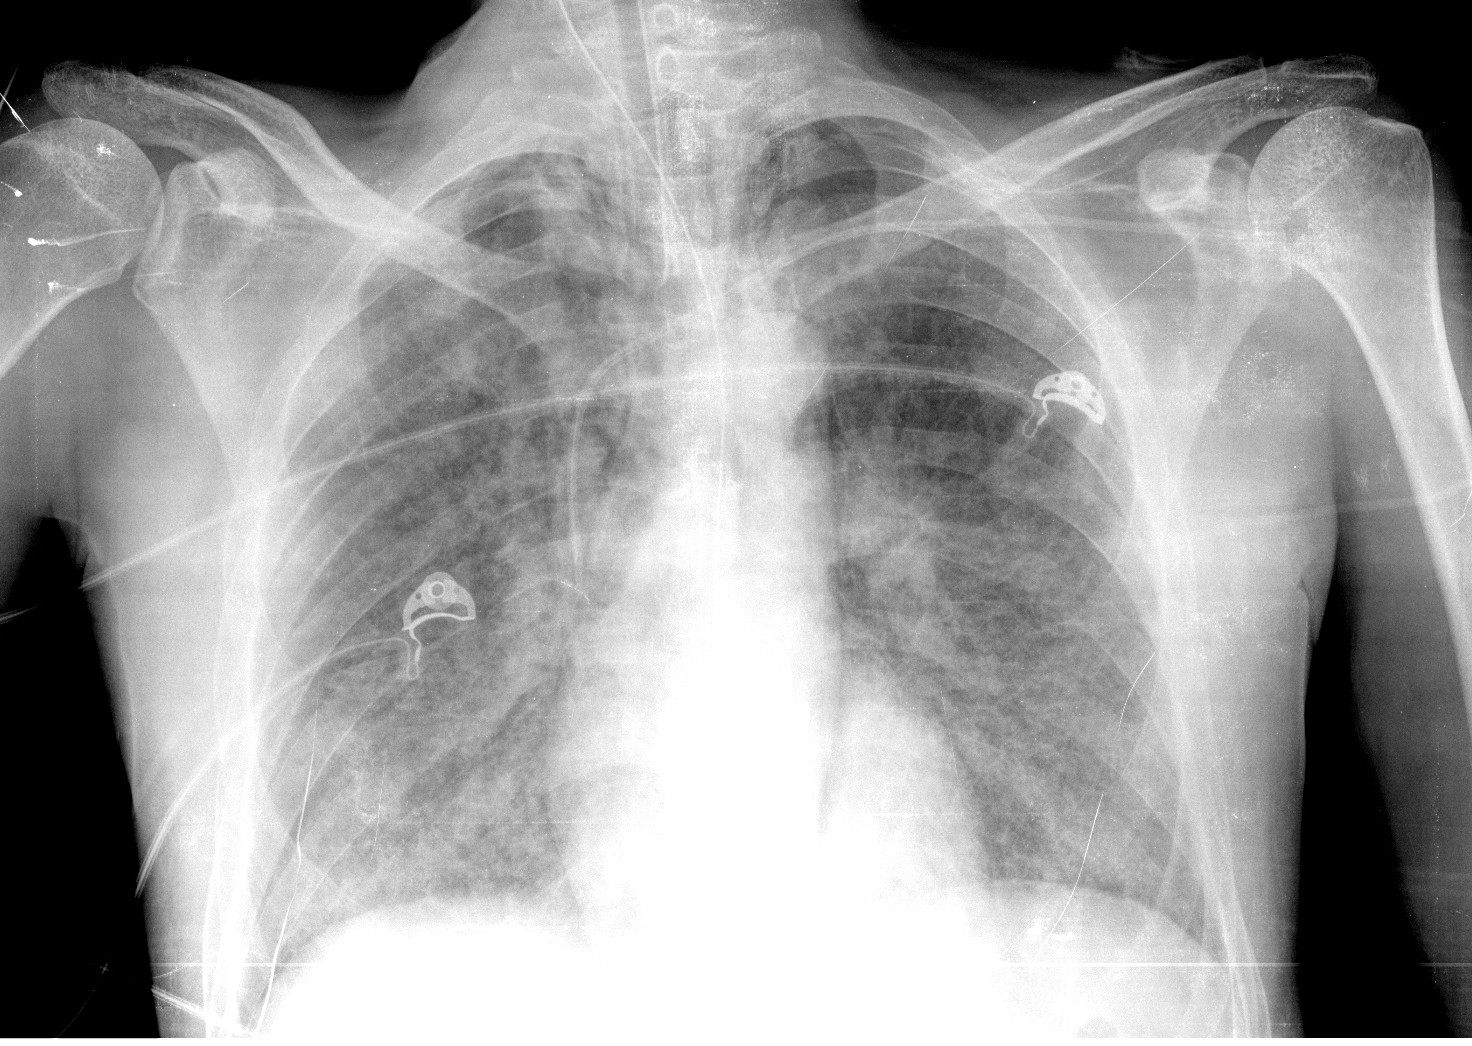

Se realiza placa de tórax, donde observamos:

Estos hallazgos descritos al pie de las radiografías son inespecíficos, pero al tratarse de un paciente inmunodeprimido, la primera posibilidad diagnóstica es una neumonía por Pneumocistis.

Radiografía: Inespecífica, 90% patológicas. Hasta 15% normales. Opacidades focales o en vidrio deslustrado, Infiltrado reticular intesticial, Neumatoceles, distribución perihiliar frecuente.